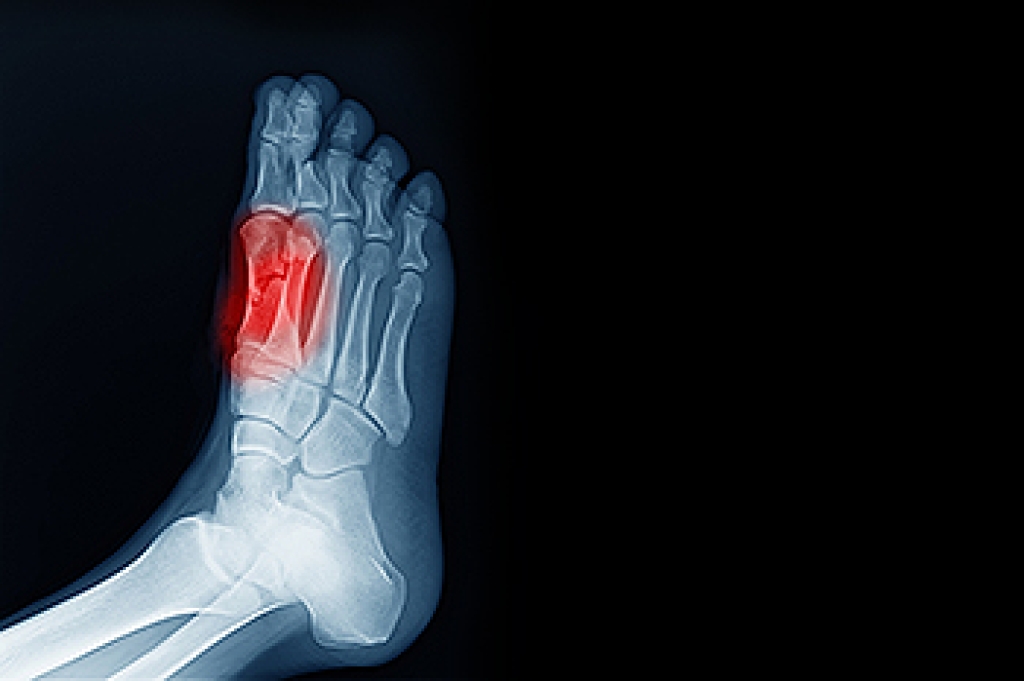

Diabetes affects millions of people every year. The condition can damage blood vessels in many parts of the body, especially the feet. Because of this, taking care of your feet is essential if you have diabetes, and having a podiatrist help monitor your foot health is highly recommended.

It is always best to inform your healthcare professional of any concerns you may have regarding your feet, especially for diabetic patients. Early treatment and routine foot examinations are keys to maintaining proper health, especially because severe complications can arise if proper treatment is not applied.